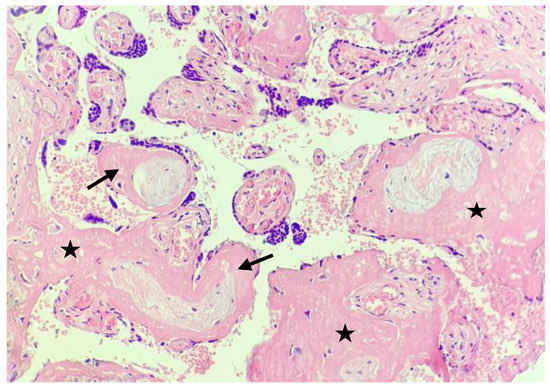

- Shanes, E.D.; Mithal, L.B.; Otero, S.; Azad, H.A.; Miller, E.S.; Goldstein, J.A. Placental Pathology in COVID-19. Am. J. Clin. Pathol. 2020, 154, 23–32. [Google Scholar] [CrossRef] [PubMed]

- Husen, M.F.; van der Meeren, L.E.; Verdijk, R.M.; Fraaij, P.L.A.; van der Eijk, A.A.; Koopmans, M.P.G.; Freeman, L.; Bogers, H.; Trietsch, M.D.; Reiss, I.K.M.; et al. Unique Severe COVID-19 Placental Signature Independent of Severity of Clinical Maternal Symptoms. Viruses 2021, 13, 1670. [Google Scholar] [CrossRef] [PubMed]

- Jaiswal, N.; Puri, M.; Agarwal, K.; Singh, S.; Yadav, R.; Tiwary, N.; Tayal, P.; Vats, B. COVID-19 as an independent risk factor for subclinical placental dysfunction. Eur. J. Obstet. Gynecol. Reprod. Biol. 2021, 259, 7–11. [Google Scholar] [CrossRef]